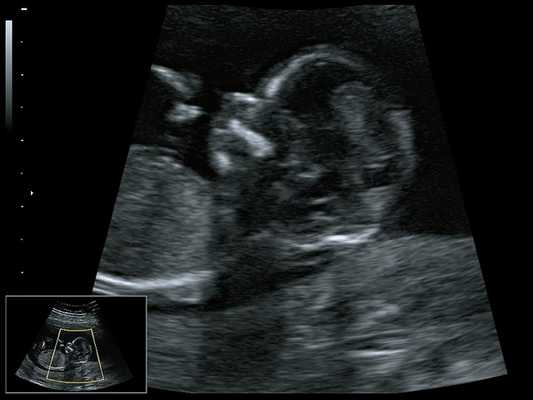

При ультразвуковом исследовании выявлены множественные особенности лицевого фенотипа у плода: микрогнатия (рис. 2-4), треугольная форма лица (рис. 5), опущенные книзу глазницы и гипоплазия скуловых дуг (рис. 6, 7), аномальная форма и положение ушей (рис. 5, 7).

Рис. 2. Микрогнатия - сагиттальный скан в 2D, беременность 13 нед.